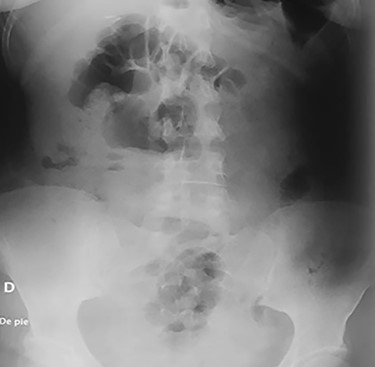

On clinical examination, a dehydrated and tachycardic (112 bpm) patient was encountered, she had diffuse pain in her lower abdomen without tenderness. After reanimation, an abdominal X-ray found two metal bodies in the bowel (Fig. 1); therefore, a computed tomography (CT) was requested, which revealed two metal foreign bodies, (razor blades) one in the stomach and one in the cecum without pneumoperitoneum (Fig. 2). As the patient did not have any tenderness, an upper endoscopy and colonoscopy were planned. During the upper endoscopy, the razor blade was detected in the antrum and was embedded in the mucosa (Fig. 3). After several failed attempts to remove the foreign object, the procedure was interrupted due to a risk of inadvertent perforation, and surgery was decided.

Abdominal X-ray on the postoperative period without any razor blades.